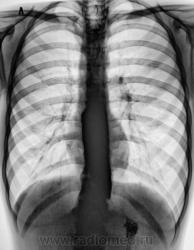

Пациент направлен на рентгенологическое исследование ЖКТр из военкомата с диагнозом - "Хронический гастрит". Пациенту неоднократно проводилась ФГДС. В течение последник 6 лет наблюдается и обследуется в области по поводу хронического гастрита и невроза пищевода. Произведено стандартное исследование.

При обзоре газа в газовом пузыре не было.

Направлен "от военкомата" - 17 лет. Мальчик худоват. На мой вопрос по поводу жалоб ответ был интересный - "после приема любой пищи - срыгиваю". Именно "срыгивает". Ест малыми порциями. Невроз и гастрит приклеены, как диагноз, в течение 6 лет.

Ахалазия пищевода. Почему ослабленный лег. рисунок в верхних поясах легочных полей.